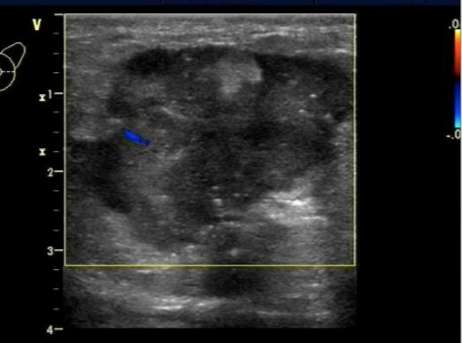

结节内回声不均,术后病理为恶性